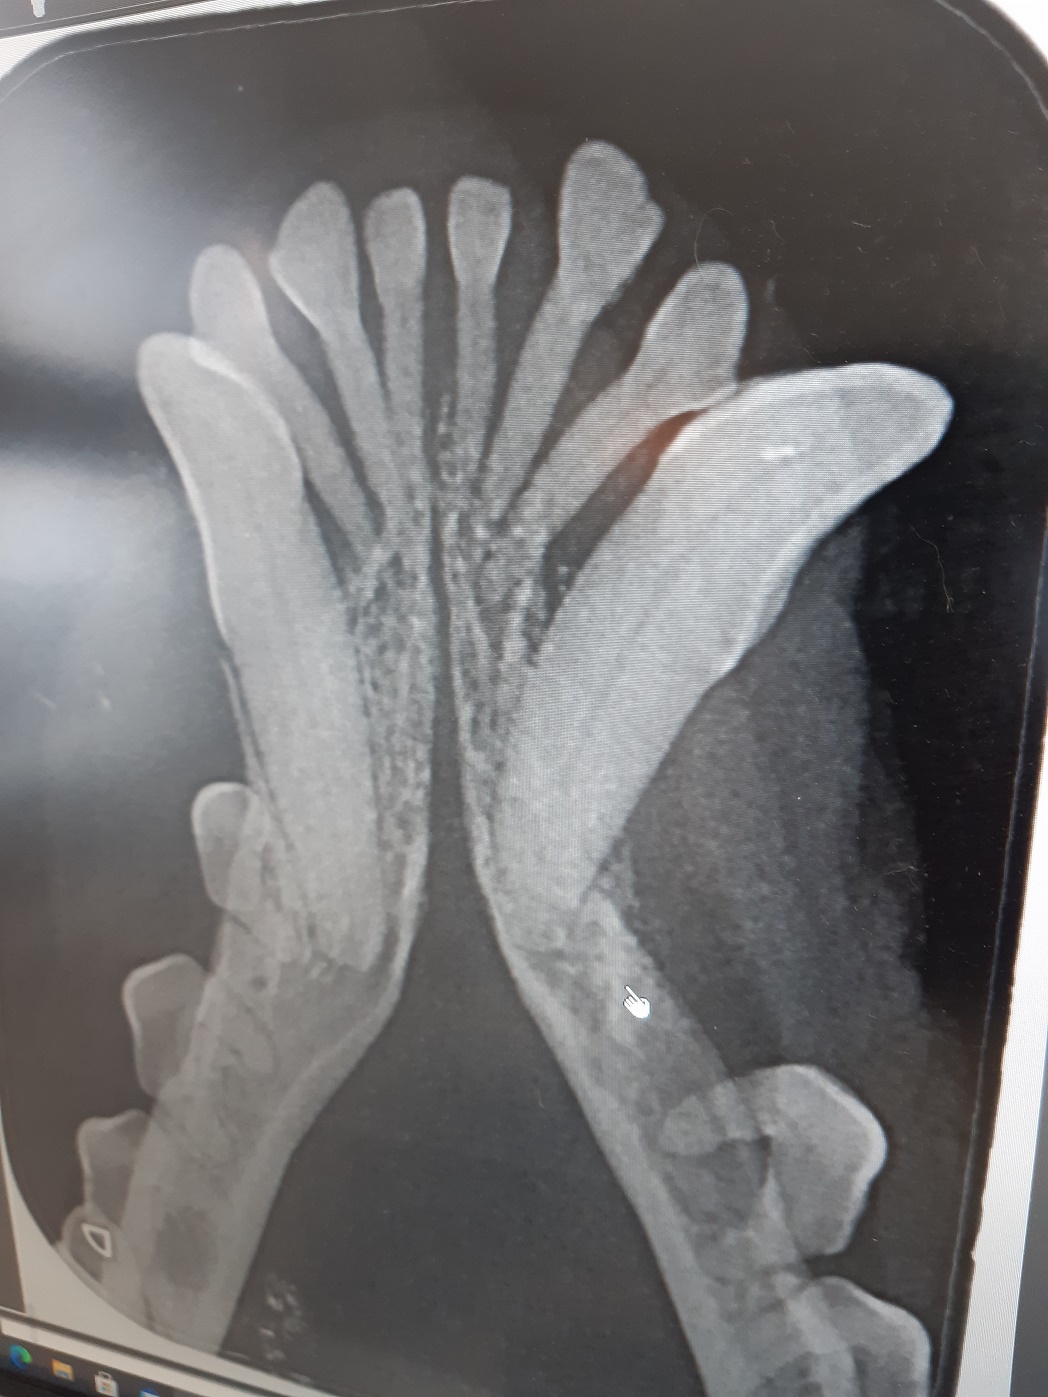

Ein kleiner Rückblick noch auf den Dezember, der uns viele interessante Patienten gebracht hat!